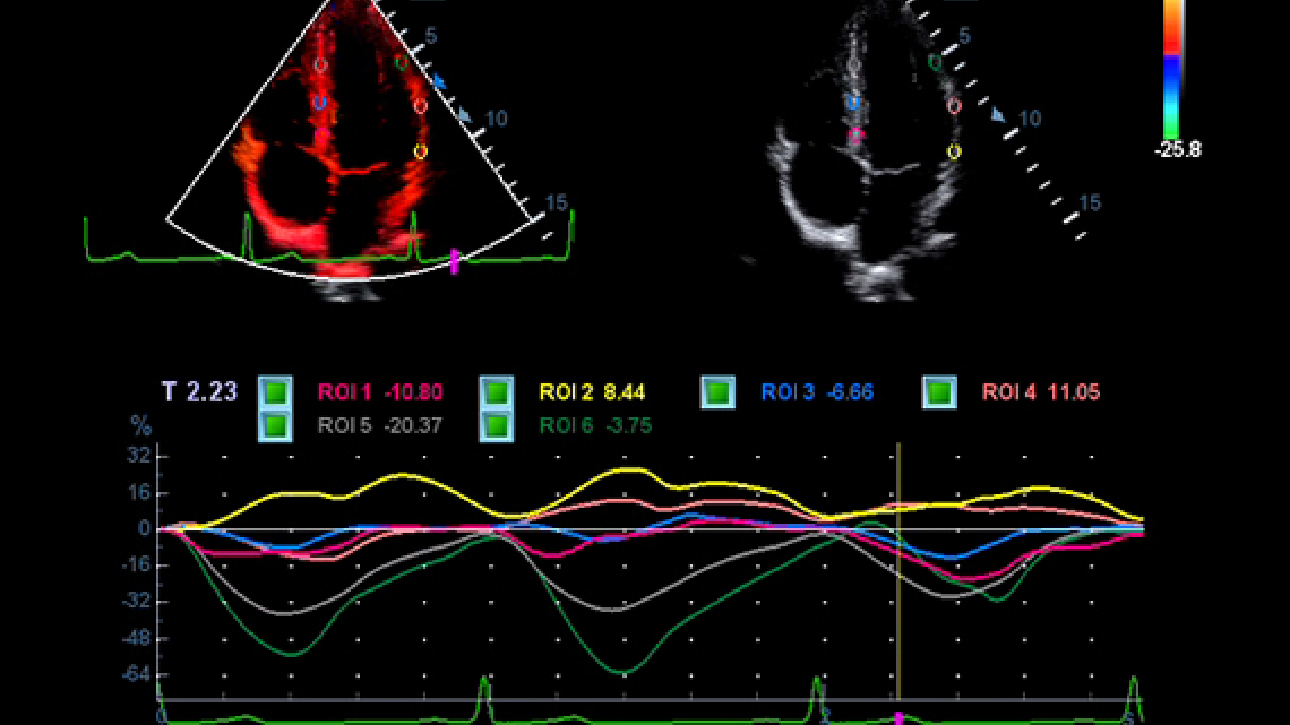

LVO (Left Ventricular Opacification)

Reveal structural and functional change of left ventricle with longer contrast agent duration and higher sensitivity with UWN+ technology.

Echo Boost

MindrayŌĆÖs unique adaptive signal processing technology with intelligent echo detection, designed to utilize the native signal-to-noise information to enhance the weak echo signals while suppressing the surrounding clutter noise, providing more balanced image brightness and improved visualization of myocardium tissue layers.